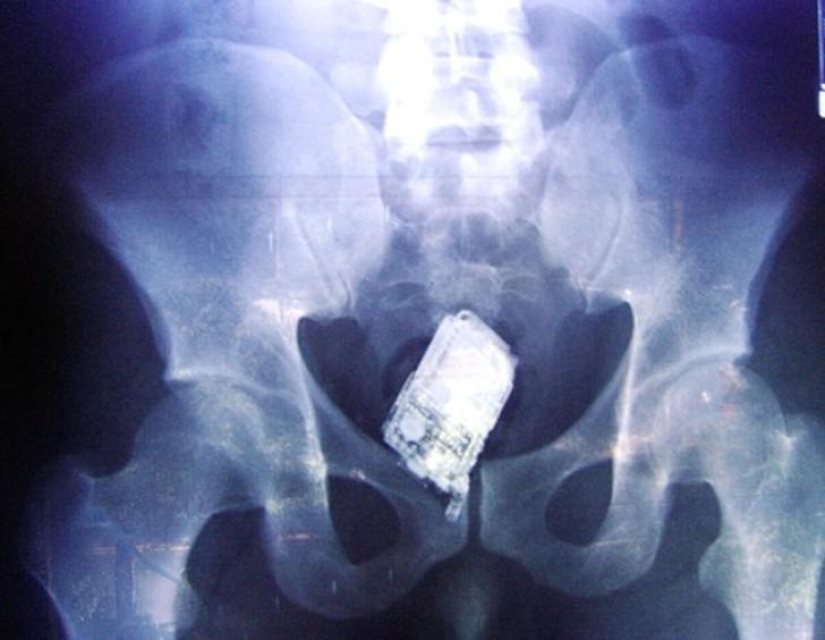

Mobile phone.